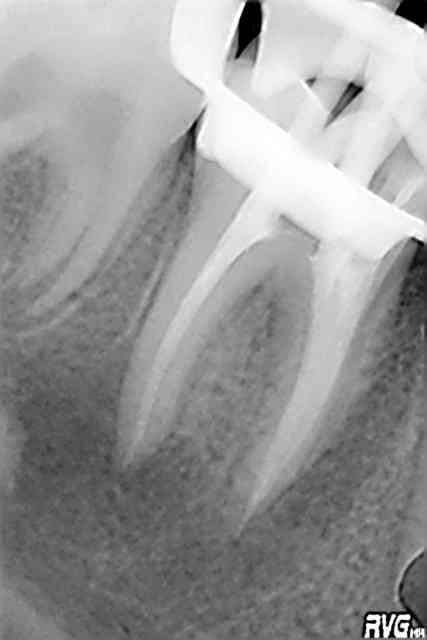

Marie, 13 ans, je vous passe les antécédents sur cette dent, mais toujours est-il qu'elle se pointe en Juillet avec douleurs lancinantes sect IV, aucune vitalité de la 46, tu m'étonnes Elton ce n'est qu'un cratère. (image 01, celle du centre)